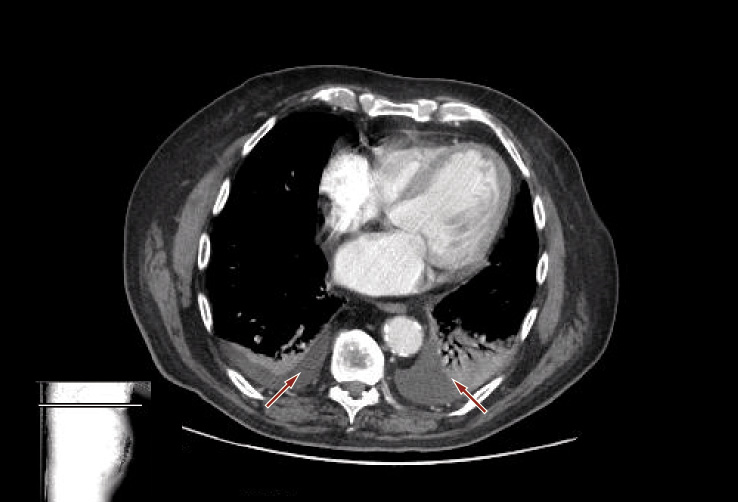

La TC torace mostrava versamento pleurico bilaterale (Figura 6).

Figura 6. TC torace: versamento pleurico bilaterale